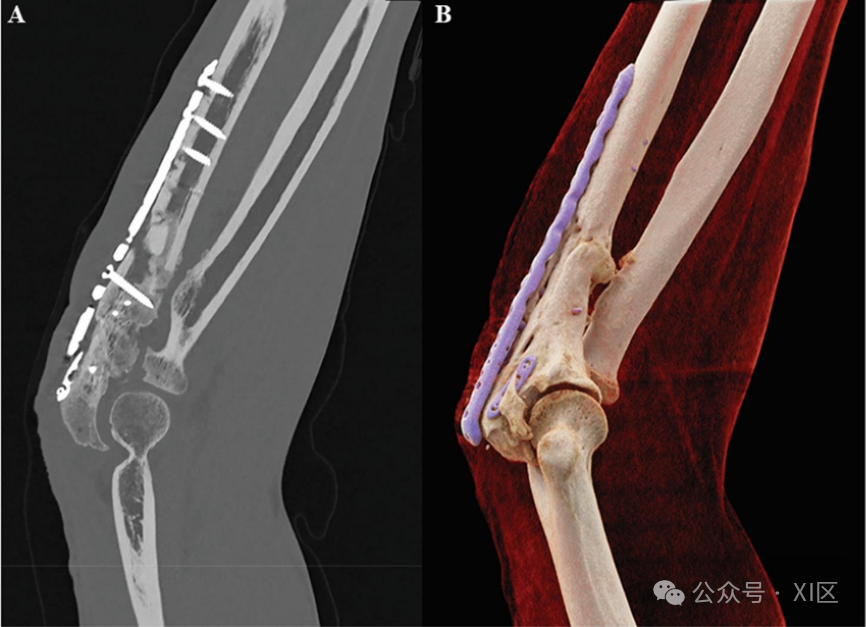

结合高能量(keV)的频谱整形技术可以提供无伪影的金属肘关节植入物骨骼成像。骨科植入物的高X射线衰减会导致金属伪影,表现为图像中的条纹和明暗区域。消除这些伪影对于评估骨科植入物的位置、骨整合和感染至关重要。A. 通过使用频谱数据集,可以从最终图像中排除低能量光子,与传统的双能量CT相比,由于更少的束硬化和光子饥饿,这可能会提高金属伪影减少的性能。B. CT扫描的电影渲染。